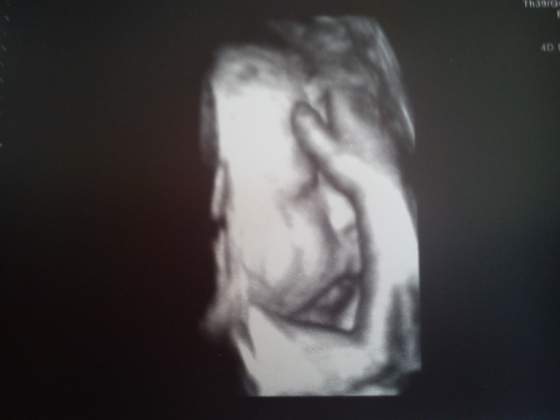

A i za to czekanie zostalam nagrodzona - zrobila mi usg 3D i natrzaskala foteczek i tu przedstawiam wam mojego Adasia - mysliciela albo zalamanego tym, ze niedlugo wyjdzie z brzuszka ^^

Waga - 1821G

Sie troche naczekalam bo az godzine obsuniecia doktorowa miala ale sie OPLACALO. Jak mowilam juz kiedys super kobieta. Adas rozwija sie prawidlowo wszystko na 32 tydzien wskazuje. Tylko ma duza stope ! 7 CM!!